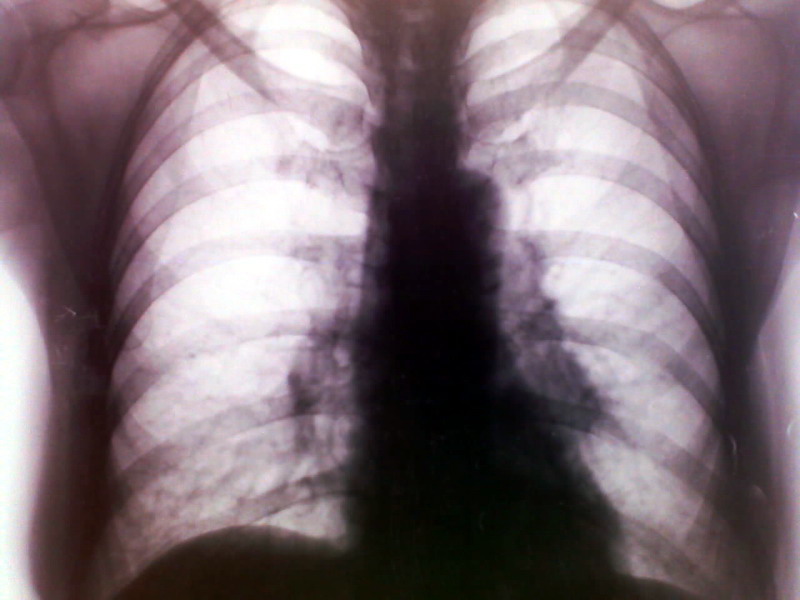

标题: X4019:女 72 胸痛 CT在另一专区 [打印本页]

左肺下叶肿块?建议ct进一步检查确诊。

左下阴影,动静脉瘘?

左下肺阴影:

左肺下叶肿块。建议ct进一步检查确诊。